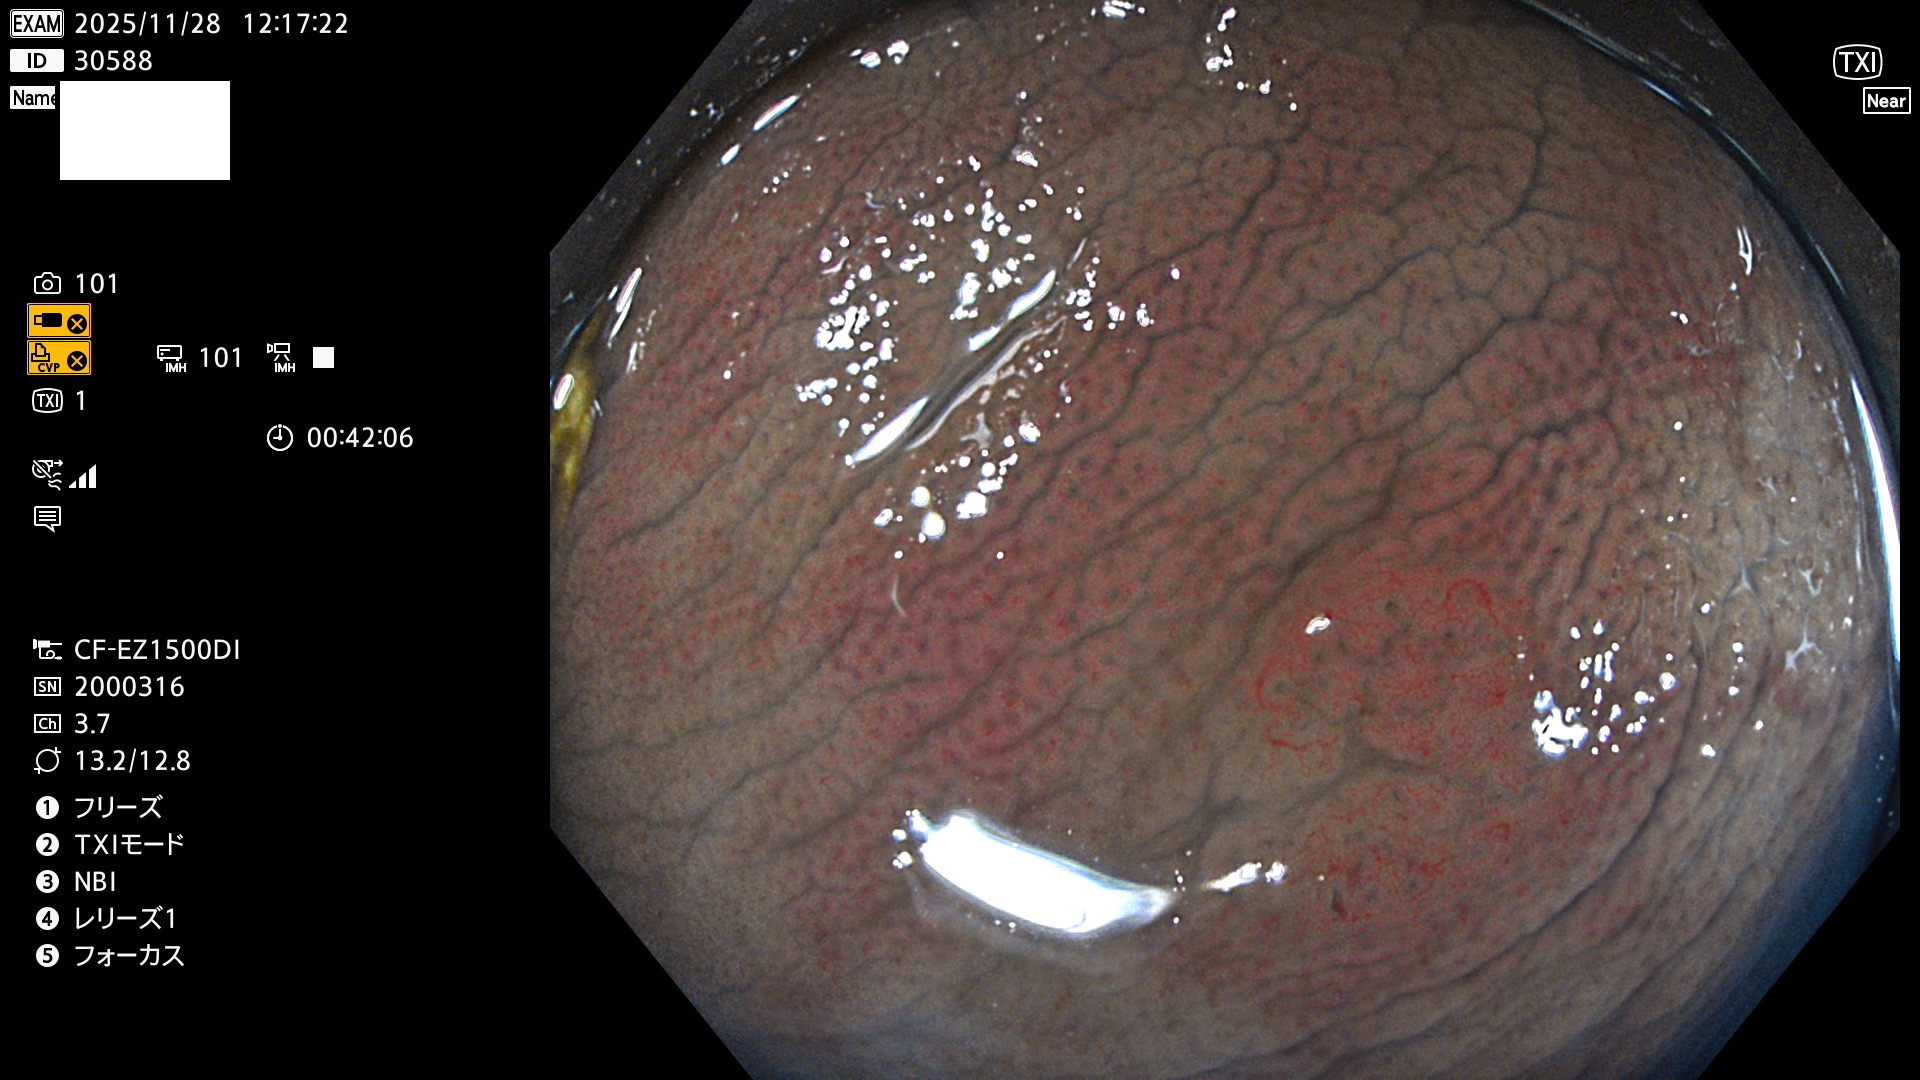

完全に平坦な物をUb、陥凹している物をUcと呼びます。Ubは認識が困難で、Ucはびらん(炎症)と紛らわしいために見落とされやすく、「内視鏡後・大腸癌」の原因になります。

毎週の検査(木・金・土・日)に発見されたUbとUc型・腺腫を、その週の日曜の夜にUPし1週間、提示します。

2025年11月27日〜12月7日の7日間(70件)6個 (Uc_ADR=6個/70人=9%)